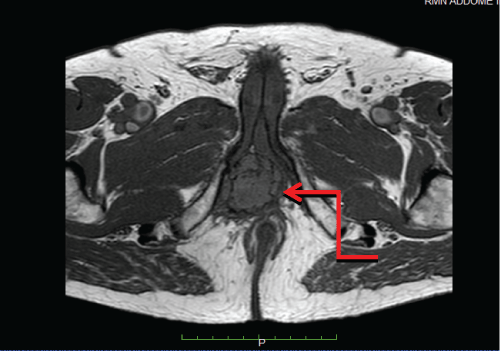

We present the case of a 71-years-old Caucasian male, with a past medical history of hypertension, Benign Prostatic Hyperplasia (BPH) and previous inguinal hernia repair. In November 2002, he underwent a laparoscopic left radical nephrectomy for a 10-cm CRCC of the left kidney with perirenal fatty tissue involvement and thrombosis of the left renal vein (pT3b N0). Patient was followed up regularly on the basis of the EAU guidelines on renal cancer. After a 14-year follow-up he presented a painless, irregular, solid mass of the perineum. MRI scan of the pelvis and perineum revealed a dishomogeneous solid expansive lesion with polylobate profiles of 52 × 58 mm, that originated from the crus of right corpus cavernosum: The mass was placed posteriorly to the base of the penis and strictly related to the internal profile of the right ischiopubic branch with partial compression and dislocation to the left of the anal canal and of the corpus spongiosum of the urethra (Figure 1a and Figure 1b). Moreover, the mass reached the limit of the membranous urethra. A trans-perineal ultrasound guided biopsy of the lesion was performed, and the pathological result showed a metastasis of CRCC. A multi-disciplinary meeting was scheduled. The patients presented favorable prognosis according to Heng and Memorial Sloan-Kettering Cancer Center (MSKCC) criteria and would have benefited from surgical resection of this single metastasis. In order to reduce surgical risk during the exeresis of the mass, the patient was treated with 4 cycles of pazopanib, as presurgical modality. Adverse effects were G1 increase in blood pression and grade 2 diarrhea symptoms. In April 2017, a follow-up-scheduled MRI scan demonstrated volumetric a 30% reduction of the perineal lesion (Figure 2a and Figure 2b). Thus, in June 2017, this patient underwent metastasectomy of the perineal mass by a median perineal access. The mass was smoothly dissected from the corpus cavernosum and the corpus spongiosum of the urethra (Figure 3a, Figure 3b and Figure 3c). The final pathological report revealed metastatic carcinoma from the right corpus cavernosum, compatible with RCC dissemination, and with negative surgical margins. According to complete resection, no TMT was proposed after surgery. At 12-month follow-up, the patient is in general good health status, and total body CT scan showed no recurrences.

Figure 2A: Sagittal MRI scan demonstrated a 30% volumetric reduction of the perineal mass (red circle). View Figure 2A

Figure 2B: Axial MRI scan demonstrated a 30% volumetric reduction of the perineal mass (red circle). View Figure 2B